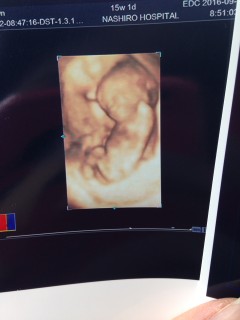

写真:15w1d:茶さん

今回、性別が女の子と判明!! 順調に成長してて、元気に動いていました! 手の平を開いたり閉じたり、とても可愛い! 早く大きくなってね!次の1カ月後の検診が楽しみ!